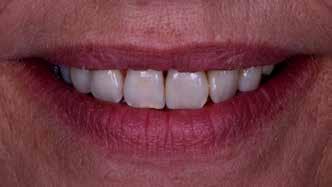

A fogászati kezelések során manapság már nem kizárólag az esztétikai megjelenés helyreállítására törekszünk. Sokszor a kedvezőtlen esztétikai megjelenés hátterében álló okok következményes módon a fogazat funkcionális működését is károsítják, így a kezelések során ezeknek a helyreállításával is foglalkoznunk kell. A különböző funkcionális és esztétikai diszkrepanciák kezelésére számtalan módszer létezik, ám ezen fogászati beavatkozások mindegyikében közös, hogy a kivitelezésük során nagyon szoros együttműködésre van szükség a kezelést végző fogorvos és a munkáját segítő fogtechnikus között. Az alábbi esetbemutatás során egy fiatal hölgypáciens fogazatának héjak alkalmazásával történő esztétikai és funkcionális rehabilitációját szeretnénk ismertetni.

A 19 éves hölgypáciens azzal a kéréssel jelentkezett a rendelőnkbe, hogy szebb fogakat szeretne. Az első konzultáció alkalmával megkérdeztük, hogy mi zavarja leginkább a fogazatának jelenlegi megjelenésében, valamint azt is megbeszéltük vele, hogy milyen végeredmény elérése esetén lenne maradéktalanul elégedett. Ebben az esetben a kezelési célokat az alábbiakban határoztuk meg:

A páciens fogazata esztétikai megjelenésének és funkcionális működésének a lehető legtöbb, saját foganyag megtartása mellett történő helyreállítása (1. és 3. ábra).

A kezelés megtervezése során kifejezett jelentősége van annak, hogy jó kommunikáció legyen a páciens, a fogorvos és a fogtechnikus között. A páciens leendő fogazatának természetes megjelenését a kezelésben részt vevő team szakmai felkészültsége, gyakorlati tapasztalata és a kezelés sikerességének irányába történő elkötelezettsége biztosítja. A beavatkozások megkezdése előtt megtörtént a páciens anamnézisének a felvétele, valamint a klinikai kivizsgálását is elvégeztük. Ezt követően lenyomatokat készítettünk a kiindulási állapotról, majd a kiindulási helyzetet extra- és intraorális fotók segítségével is rögzítettük (13. a-c. ábra).

A kezeléstervezés egyik legfontosabb lépése a mock-up elkészítése. A mock-up alapjául szolgáló wax-up-ot (felviaszolás) is ugyanolyan részletességgel kell a fogtechnikusnak elkészíteni, mintha azok már a végleges fogpótlások alapjául szolgáló mintázatok lennének. A mock-upnak nagyon pontosan kell illeszkednie, valamint a tervezett fogpótlás meg-

jelenését is rendkívül élethűen kell reprezentálnia. Ahhoz, hogy a páciens mock-uppal kapcsolatos első benyomásai kedvezőek legyenek, a mock-up színének a páciens „szemfehérjének” színével meg kell egyeznie. A kezelési cél páciens által történő elfogadása és a tervezett eredménnyel kapcsolatos „wow-effektus” kialakulása nagyban függ a páciensben az első megtekintés során kialakult első benyomásoktól.

Az eddigi tapasztalataink szerint a páciensek jelentős többsége egyértelműen kifejezi az elégedettségét, ha a mock-up megfelel az eredeti elképzeléseiknek. A bemutatásra kerülő esetben is ez történt. A tervezett végeredmény megtekintését követően a páciens azonnal kérte az általunk javasolt kezelési tervben ismertetett beavatkozások elvégzését. A héjak alapanyagául az Ivoclar Vivadent által gyártott A1-es színű Telio CS kerámiát javasoltuk. Az anyagválasztás hátterében az állt, hogy ez az anyag nagy keménységgel rendelkezik, valamint az, hogy a felszínét nagy simaságúra lehet polírozni. A páciens rendkívül fiatal életkora is azt a terápiás koncepciót erősítette, hogy a kezelés során lehetőség szerint kizárólag non-invazív beavatkozásokat alkalmazzunk.

A páciens már kezdetben is rendkívüli érdeklődést mutatott a preparálást nem igénylő (non-prep), héjakkal történő ellátással kapcsolatban. Ennek a terápiás modalitásnak az előnyei közé tartozik, hogy a fogakat egyáltalán nem, vagy csak minimál invazív módon kell preparálni, nincs szükség ideiglenes héjak készítésére, a héjak alapanyagául szolgáló kerámia nem hajlamos az elszíneződésre, nem jellemző a beavatkozások elvégzését követően jelentkező posztoperatív szenzitivitás, valamint hogy ezzel a módszerrel rendkívül kedvező esztétikai végeredményt lehet elérni. A fenti előnyök rendkívül meggyőzően hatottak a páciensre. A döntése során azt is figyelembe vette, hogy amennyiben ezeket a viszonylag költséges restaurátumokat választja, akkor ez a kezelés végösszegét is jelentős mértékben befolyásolja.

A kezelés során az jelentette a legnagyobb kihívást, hogy a héjakkal ellátott fogak élethűen utánozzák a természetes fogazat megjelenését. A fogpótlás színének, valamint a restaurátumok felszíni textúrájának és alakjának harmonikusan kell a páciens arcesztétikájához és karakteréhez illeszkednie.

A tényleges protetikai ellátás megkezdése előtt a páciens mosolygás közben látható fogait otthoni fogfehérítés keretei között a kérésének megfelelő A1-es fogszín eléréséig fehérítettük. A fehérítés során a későbbiekben héjakkal ellátásra kerülő fogak színén nem változtattunk. A fogak előkészítése részeként csupán a két felső nagymetsző (1.1,2.1) incizális élét kellett kismértékben redukálni. A többi felső front fog (1.3,1.2,2.2,2.3) nem került preparálásra.

nak megfelelően – előkészítjük (orthofoszforsavval történő savazás, lemosás, szárítás és bond réteggel történő fedés). Ezzel egyidejűleg a ragasztásra kerülő héjak is előkészítésre kerülnek (hidrofolysavval történő savazás, lemosás, szárítás, szilanizálás, bond réteggel történő fedés, és végül az alkalmazni kívánt ragasztóanyag felvitele). Ezután a héjakat a fogak felszínén egyesével pozicionáljuk, majd néhány másodpercen keresztül polimerizációs lámpa segítségével megvilágítjuk. Ezt követően a kifolyó ragasztófelesleget eltávolítjuk, majd elvégezzük a restaurátumok végső polimerizálását. A héjak végleges rögzítését követően az esetlegesen visszamaradt ragasztómaradványok eltávolításra kerülnek, valamint ellenőrizzük az okklúzió és artikuláció közben létrejövő fogérintkezéseket. Az optimális esztétikai eredmény biztosítása érdekében kiemelt jelentősége van a papillák helyreállításának (rózsaszín esztétika). A modern fogorvoslás egyik kiemelt célja a fehér- és rózsaszín esztétika közti harmonikus egyensúly megteremtése. A papillák színe, nagysága és szimmetrikus megjelenése meghatározó szerepet tölt be a rózsaszín esztétika kialakításában. Az íny lefutása ugyancsak rendkívül jelentős mértékben befolyásolja a páciens fogazatának esztétikus megjelenését.

A cikkünkben bemutatásra kerülő eset ellátása során preparációt nem igénylő héjak készítése mellett döntöttünk. A héjak készre vitele során a platinafólia technikát alkalmaztuk. Annak ellenére, hogy az elkészítésre kerülő héjak rendkívül vékonyak, és ezáltal a végleges rögzítésük előtt jelentős törésveszéllyel állunk szemben, összességében mégis olyan minimál invazív kezelési eljárásnak számítanak, amely segítségével kifogástalan esztétikai eredményeket lehet elérni. A fent leírtak alapján bátran javasoljuk e módszer alkalmazását.